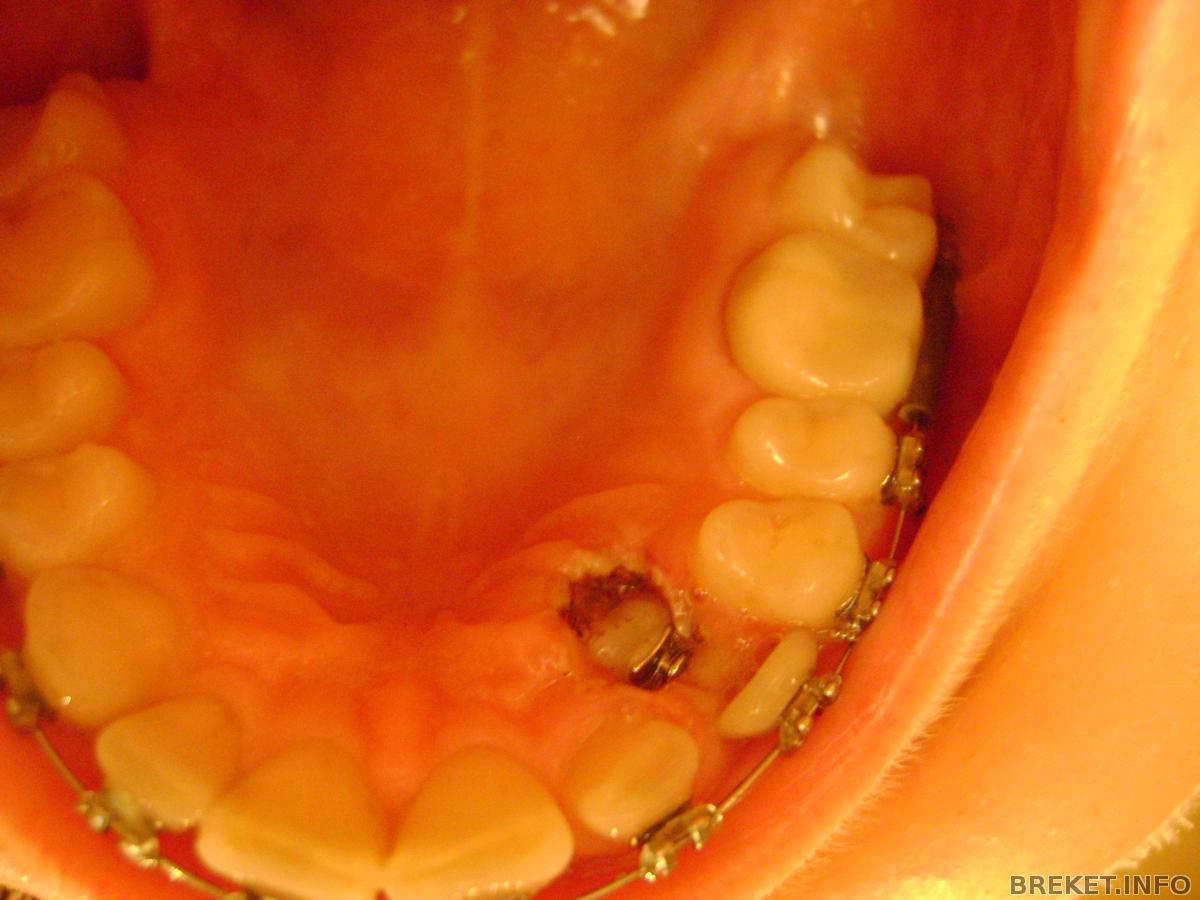

вот как-то так все это и выглядит, страшнова-то, но на деле все отлично.